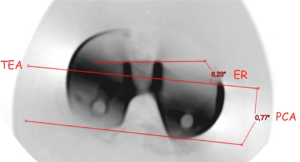

After selecting a single best axial scan, the femoral surgical transepicondylar axis (sTEA), the femoral posterior condylar axis (PCA) and the projection of the medial third of the tibial tubercle on the anterior tibial cortex were identified. For each knee, the sTEA, the PCA and the medial third of the tibial tubercle were projected on a tibial axial cut. The geometric center of the tibial area was also identified. A line was first drawn from the center of the tibial plate to the medial third of the tubercle and then the perpendicular line to the TEA passing through the tibial plate center was identified. At this point, the Akagi’s line was drawn. This landmark was made by a line starting at the medial third of the tibial tubercle and ending at the center of the posterior cruciate ligament tibial insertion. The most appropriate tibial baseplate tracing (size 3 to 8) for the Nex-Gen Total Knee System (Zimmer, Warsaw, USA) was superimposed at this time, matching the anterior tibial cortex with its anterior surface (“Curve-on-Curve Technique”). The rotation of the tibial plate tracing was calculated with respect to the sTEA, the medial third of the tibial tubercle line, the Akagi’s line and the PCA (Figure 1).

Total knee arthroplasty (TKA) components evaluation

All knees underwent computed tomography (CT) evaluation in the postoperative period utilizing a GE Healthcare scanning system (Little Chalfont, UK). The scanning protocol included positioning the knee in full extension with the second metatarsal axis in a vertical position according to Berger et al. (22), which has been followed to obtain a reproducible knee position for all CT scans. All images were 2 mm in thickness and with 3 mm in reconstructive increments from the distal metaphysis to the tibial tubercle. Specific software (SECTRA AB, Sectra, Sweden) was utilized for artifact suppression. On the best single femoral axial scan, the sTEA was selected and the femoral PCA was measured. At this point, the sTEA was projected on the tibial axial cut where the ML axis of the tibial baseplate was best identifiable through its “dwell points” (for the symmetric component) or the anterior axis of the polyethylene locking mechanism (for the asymmetric component); the rotation of the tibial component respect to the sTEA was then measured (Figure 5).